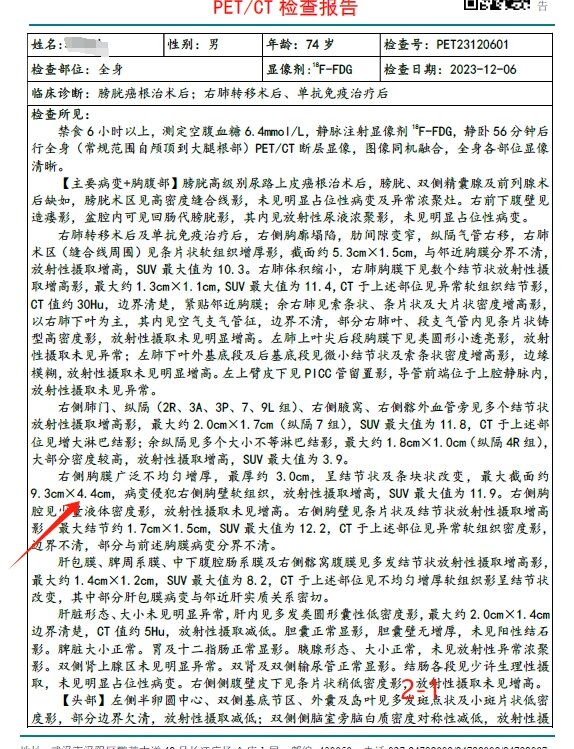

放疗前PET/CT(2023-12-06):

1

2